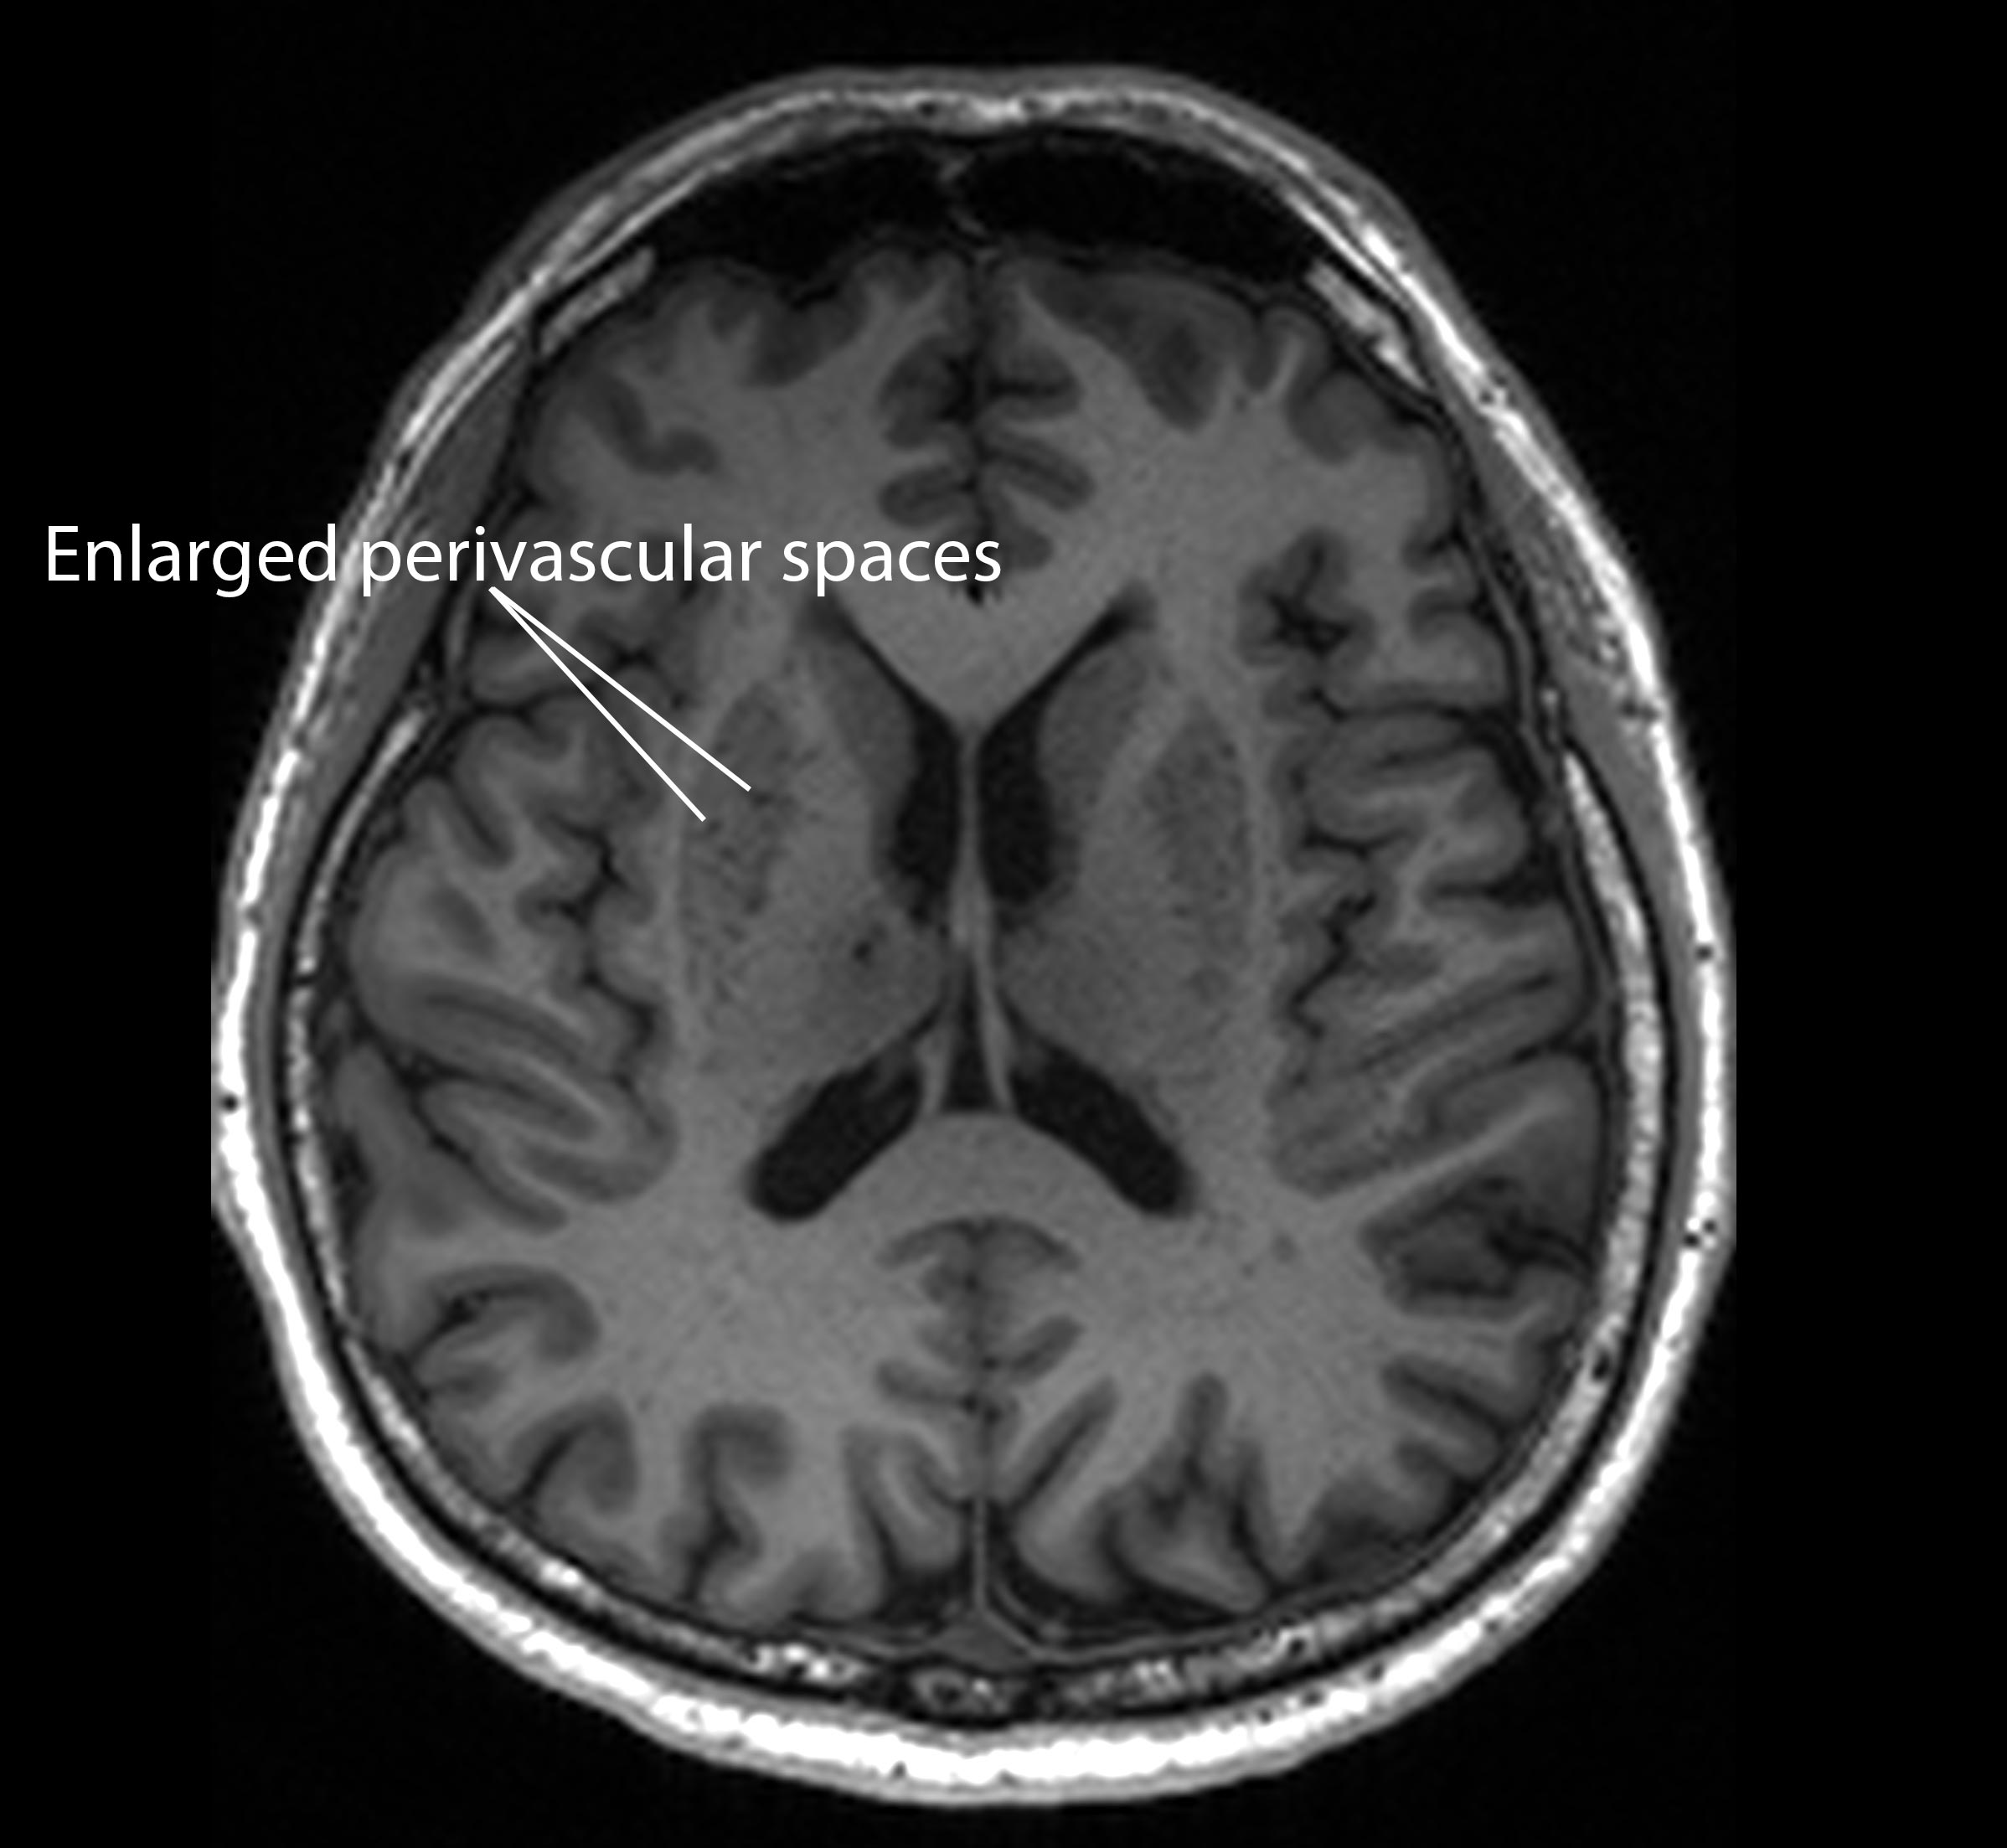

Blocks to these drains, termed “enlarged perivascular spaces”, could serve as an important early signal of dementia, according to the study published in the journal Neurology.

“These brain anomalies can be visually identified on routine magnetic resonance imaging (MRI) scans performed to evaluate cognitive decline,” said neurologist Nagaendran Kandiah from Nanyang Technological University, Singapore (NTU Singapore).

When this drainage system becomes inefficient, these spaces can expand in a way that is detectable on MRI scans, researchers say.